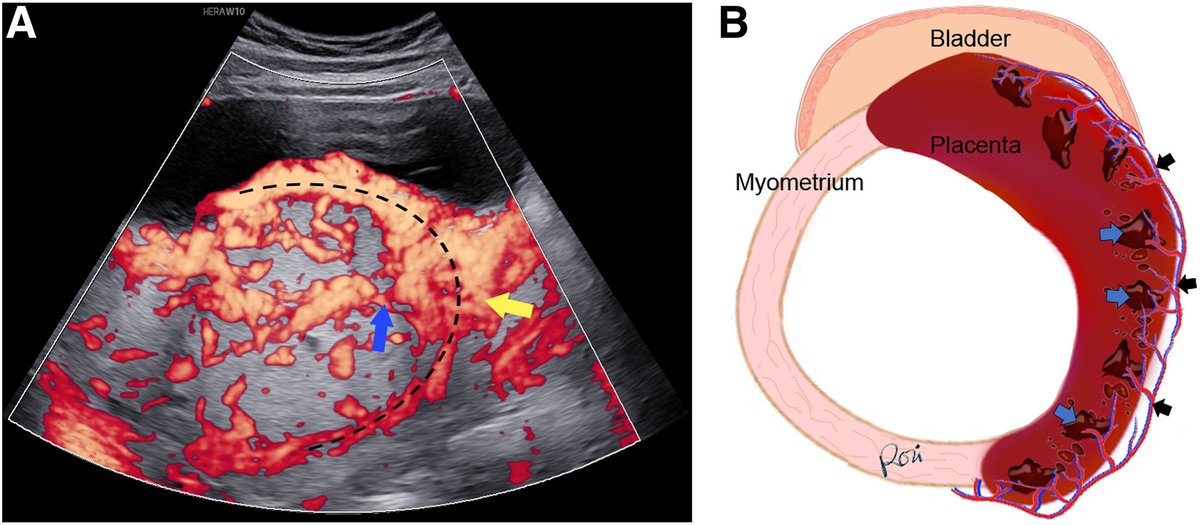

Diagnostic ultrasound to inform the surgical approach to cesarean delivery in patients at high risk for placenta accreta spectrum disorders https://t.co/rc7akSVIIT